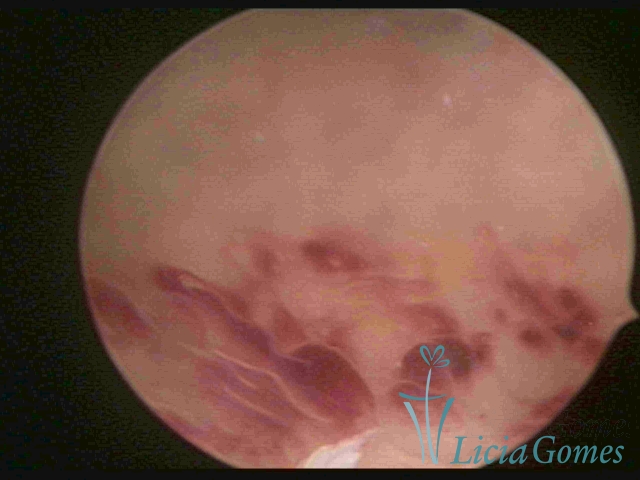

ENDOMETRITE AGUDA

Na vídeo-histeroscopia observamos o endométrio sangrante, sua superfície endometrial é espiculada, com aspecto “cremoso” e coloração esbranquiçada com brilho acentuado pela fibrina acumulada. Áreas azuladas ou acidentadas que podem corresponder à necrose cística. Pode haver muco aderente ou piometra.